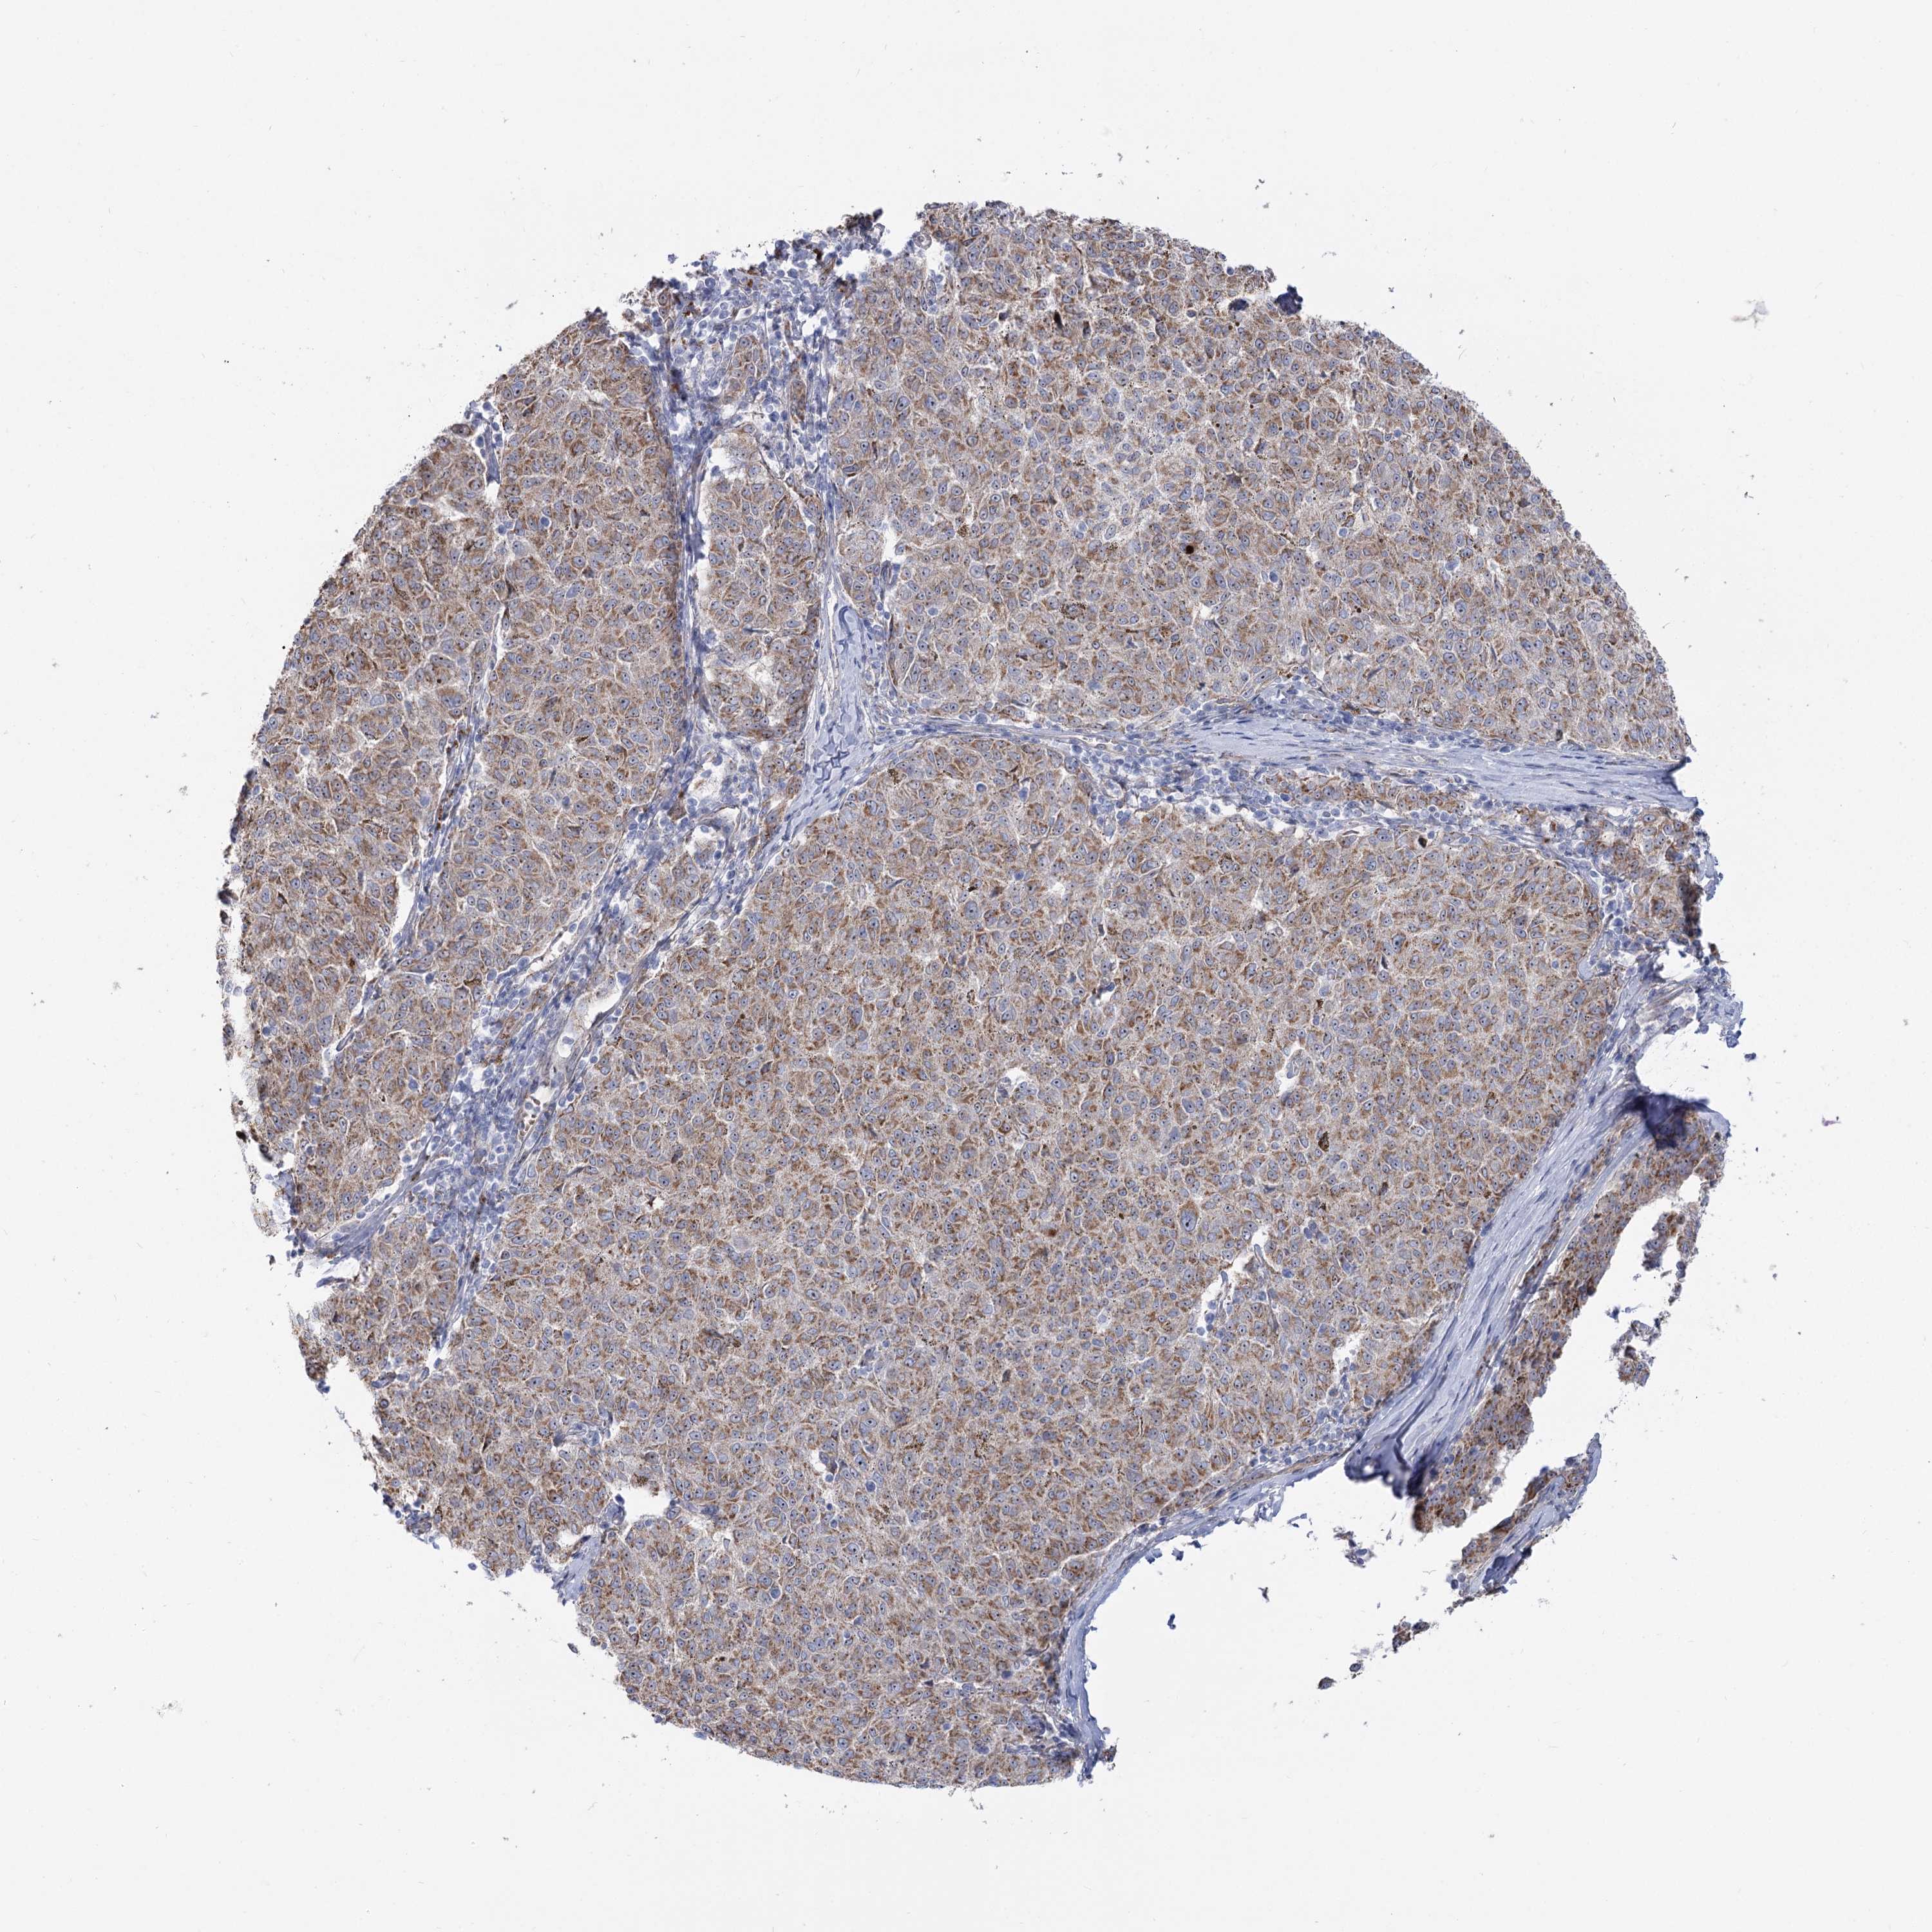

MELANOMA - Protein expressioni

A mouse-over function shows sample information and annotation data. Click on an image to view it in a full screen mode. Samples can be filtered based on level of antibody staining by selecting one or several of the following categories: high, medium, low and not detected. The assay and annotation is described here.

Note that samples used for immunohistochemistry by the Human Protein Atlas do not correspond to samples in the TCGA dataset.

Antibody stainingi

Antibody staining in the annotated cell types in the current human tissue is reported as not detected, low, medium, or high, based on conventional immunohistochemistry profiling in selected tissues. This score is based on the combination of the staining intensity and fraction of stained cells.

Each image is clickable and will lead to virtual microscopy that enables deeper exploration of all samples and also displays staining intensity scores, fraction scores and subcellular localization as well as patient and tissue information for each sample.

Antibody HPA038208

Antibody HPA038209

Staining

High

Medium

Low

Not detected

Intensity

Strong

Moderate

Weak

Negative

Quantity

>75%

75%-25%

<25%

None

Location

Nuclear

Cytoplasmic/membranous

Cytoplasmic/membranous,nuclear

Malignant melanoma, NOS

Malignant melanoma, Metastatic site